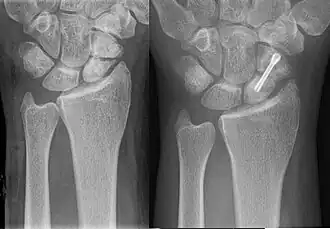

- Immobilization of the fracture with internal or external fixation. Metal plates, pins, screws, and rods, that are screwed or driven into a bone, are used to stabilize the broken bone fragments.